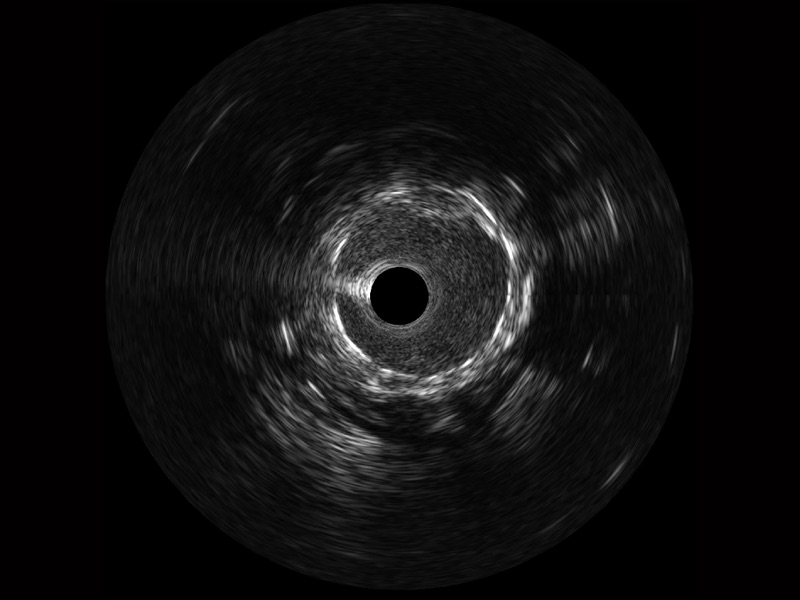

• 乐玩lewin国际宽频IVUS图像

• 传统IVUS图像

对比传统IVUS导管成像,乐玩lewin国际宽频IVUS图像的近场支架梁显影更细腻,远场中膜外血管仍清晰可辨,兼顾远中近,兼顾分辨力与穿透深度